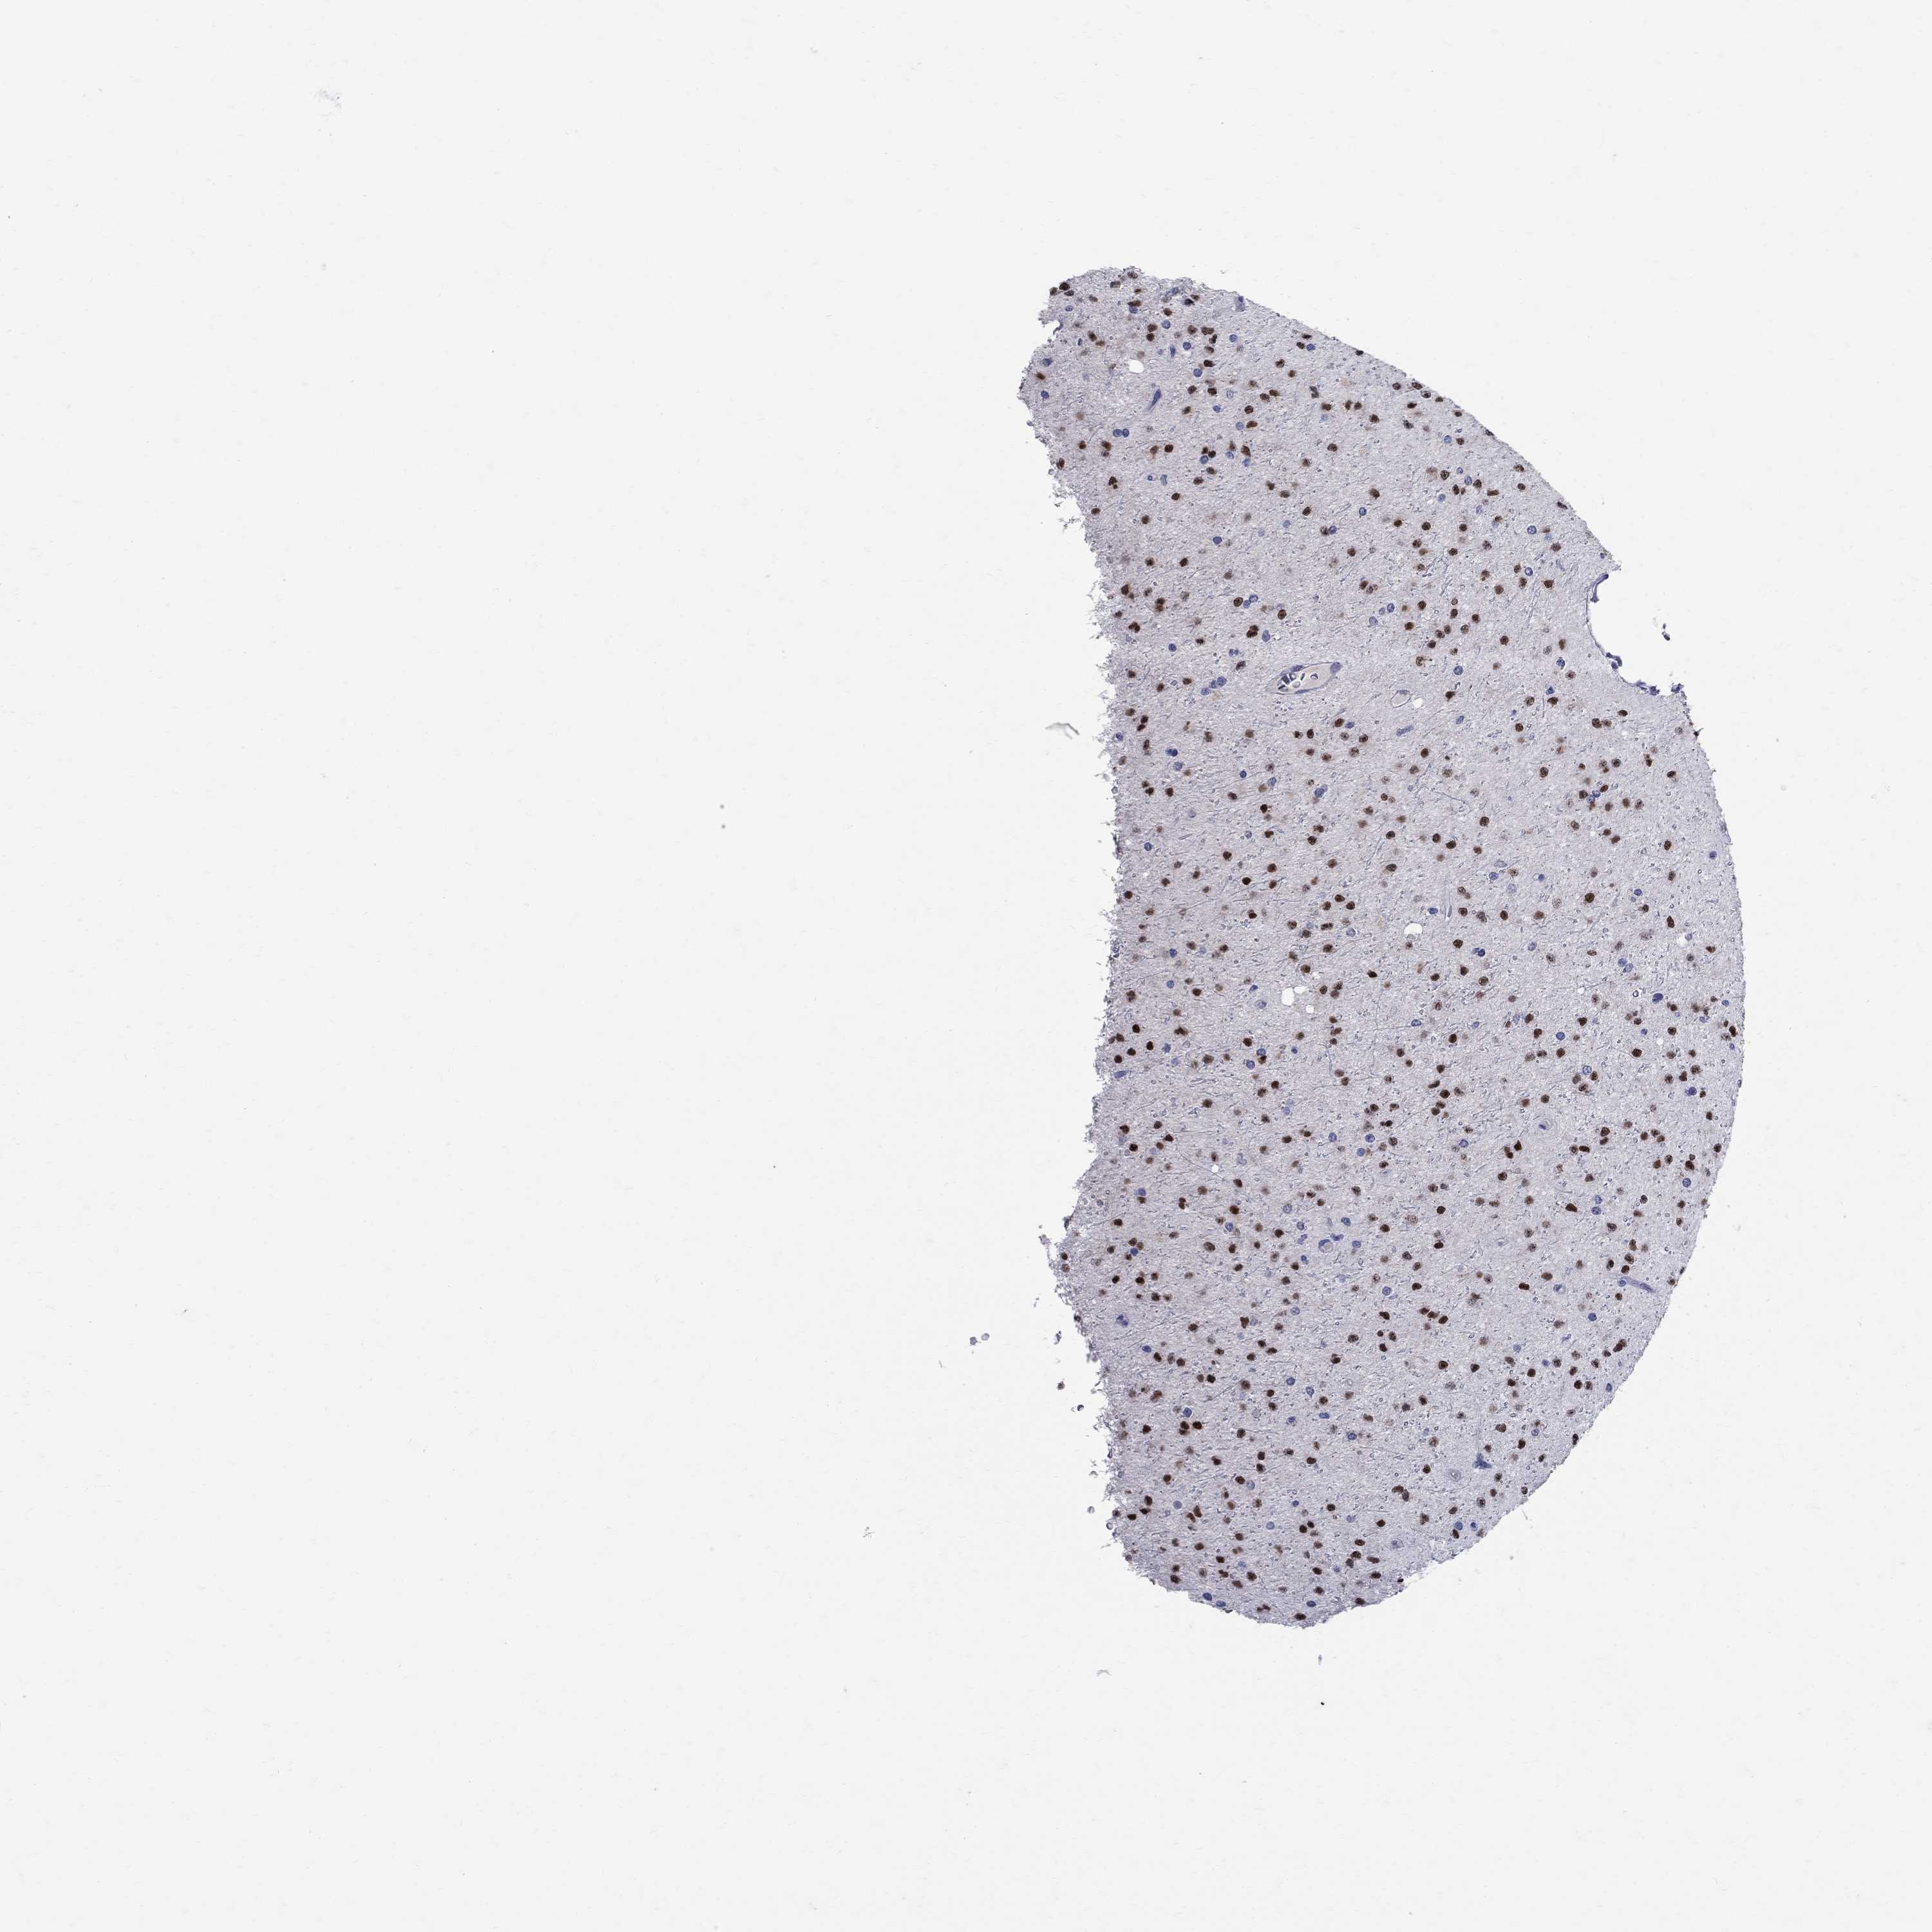

GLIOMA - Protein expressioni

A mouse-over function shows sample information and annotation data. Click on an image to view it in a full screen mode. Samples can be filtered based on level of antibody staining by selecting one or several of the following categories: high, medium, low and not detected. The assay and annotation is described here.

Note that samples used for immunohistochemistry by the Human Protein Atlas do not correspond to samples in the TCGA dataset.

Antibody stainingi

Antibody staining in the annotated cell types in the current human tissue is reported as not detected, low, medium, or high, based on conventional immunohistochemistry profiling in selected tissues. This score is based on the combination of the staining intensity and fraction of stained cells.

Each image is clickable and will lead to virtual microscopy that enables deeper exploration of all samples and also displays staining intensity scores, fraction scores and subcellular localization as well as patient and tissue information for each sample.

Antibody HPA045725

Antibody CAB079745

Staining

High

Medium

Low

Not detected

Intensity

Strong

Moderate

Weak

Negative

Quantity

>75%

75%-25%

<25%

None

Location

Nuclear

Cytoplasmic/membranous

Cytoplasmic/membranous,nuclear

Glioma, malignant, Low grade

Glioma, malignant, High grade